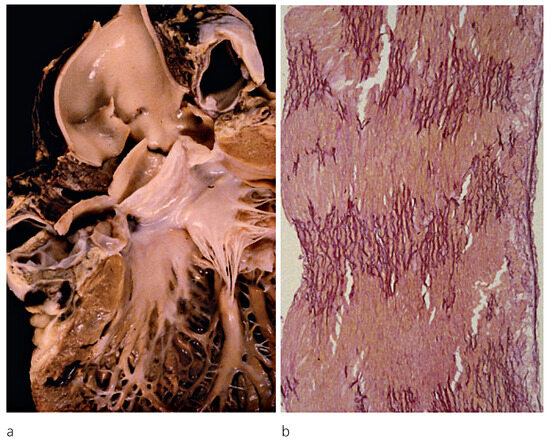

Myocardium